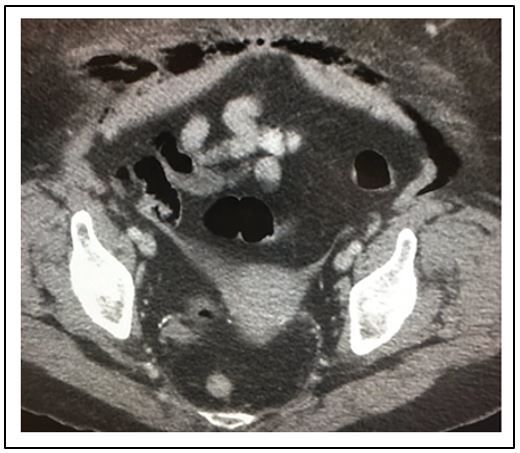

Figure 1. CT scan pelvis (Please click to enlarge; use back arrow to return to case)

Answers What does the CT scan show: The CT shows an atrophic uterus with gas (black) tracking just behind the abdominal wall extending over the rectus sheath (Figure 1; Figure 2A). A lower cut (Figure 2B) shows gas tracking into the labia majora on the right (click on Figures to enlarge).